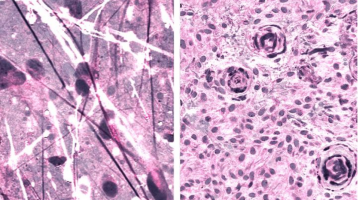

The imaging technique, stimulated Raman histology (SRH), reveals tumour infiltration in human tissue by collecting scattered laser light, illuminating essential features not typically seen in standard histologic images.

The microscopic images are then processed and analysed with artificial intelligence, and in under two and a half minutes, surgeons are able to see a predicted brain tumour diagnosis.